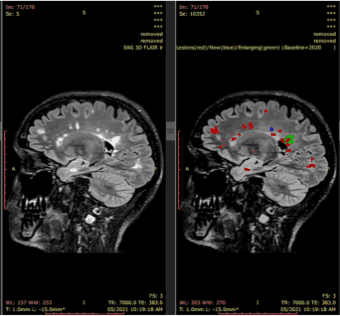

Digital Health - (Thursday October 19, 2023) A global survey by Censuswide has revealed that the healthcare sector is only just behind the tech space for employee AI usage. This is despite having the lowest levels of security investment in AI protection.Surveying… ![]() A real-world clinical validation for AI-based MRI monitoring in multiple sclerosis

npj Digital Medicine - (Thursday October 19, 2023) Modern management of MS targets No Evidence of Disease Activity (NEDA): no clinical relapses, no magnetic resonance imaging (MRI) disease activity and no disability worsening. While MRI is the principal tool available to neurologists… |